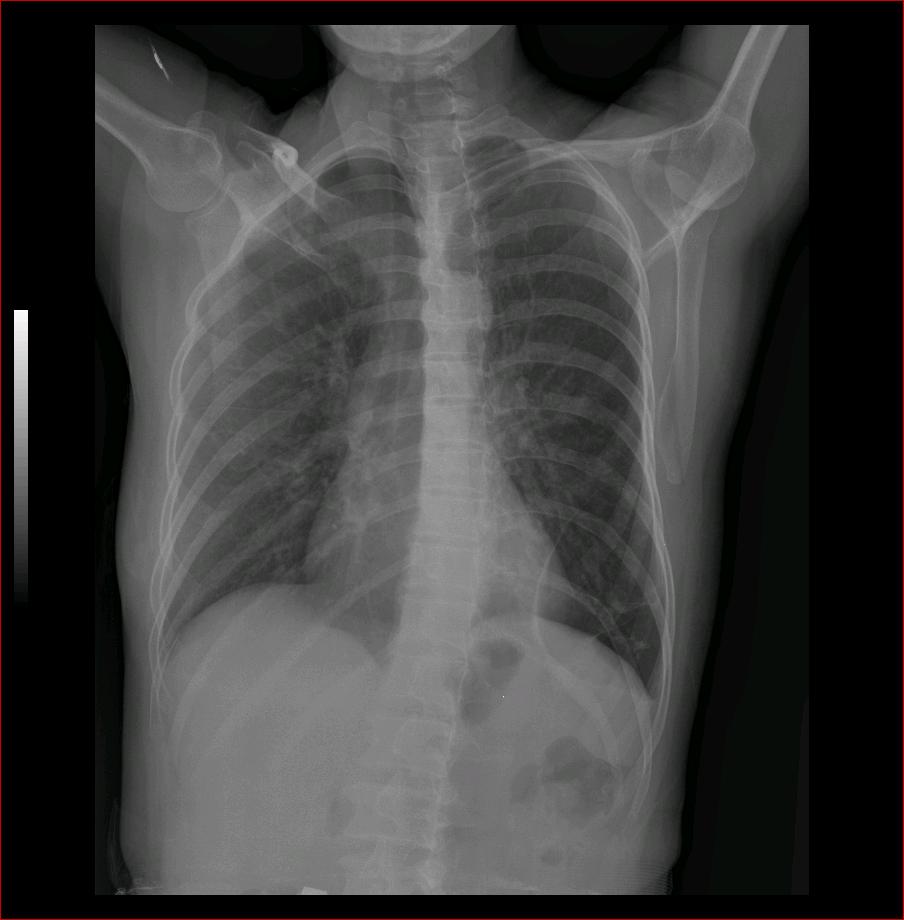

标题: CT9509:女,50岁,咳嗽,发热,38度, [打印本页]

标题: CT9509:女,50岁,咳嗽,发热,38度,

左肺上叶舌段炎症,左肺下叶支气管扩张并感染

现有的征象提示左肺支扩并双肺炎症。至于隔离肺可以考虑但缺少证据。

双肺炎症;左下支扩并感染,肺隔离症待排

左肺舌叶及右肺下叶背段斑片状低密度影,左肺下叶内基底段网格状阴影,周围肺野透亮度增高,结合临床咳嗽、发热,38度,无咯血及反复感染病史,考虑双肺炎症,左下肺发育不良。建议抗炎治疗后复查或增强与左下肺隔离症鉴别。